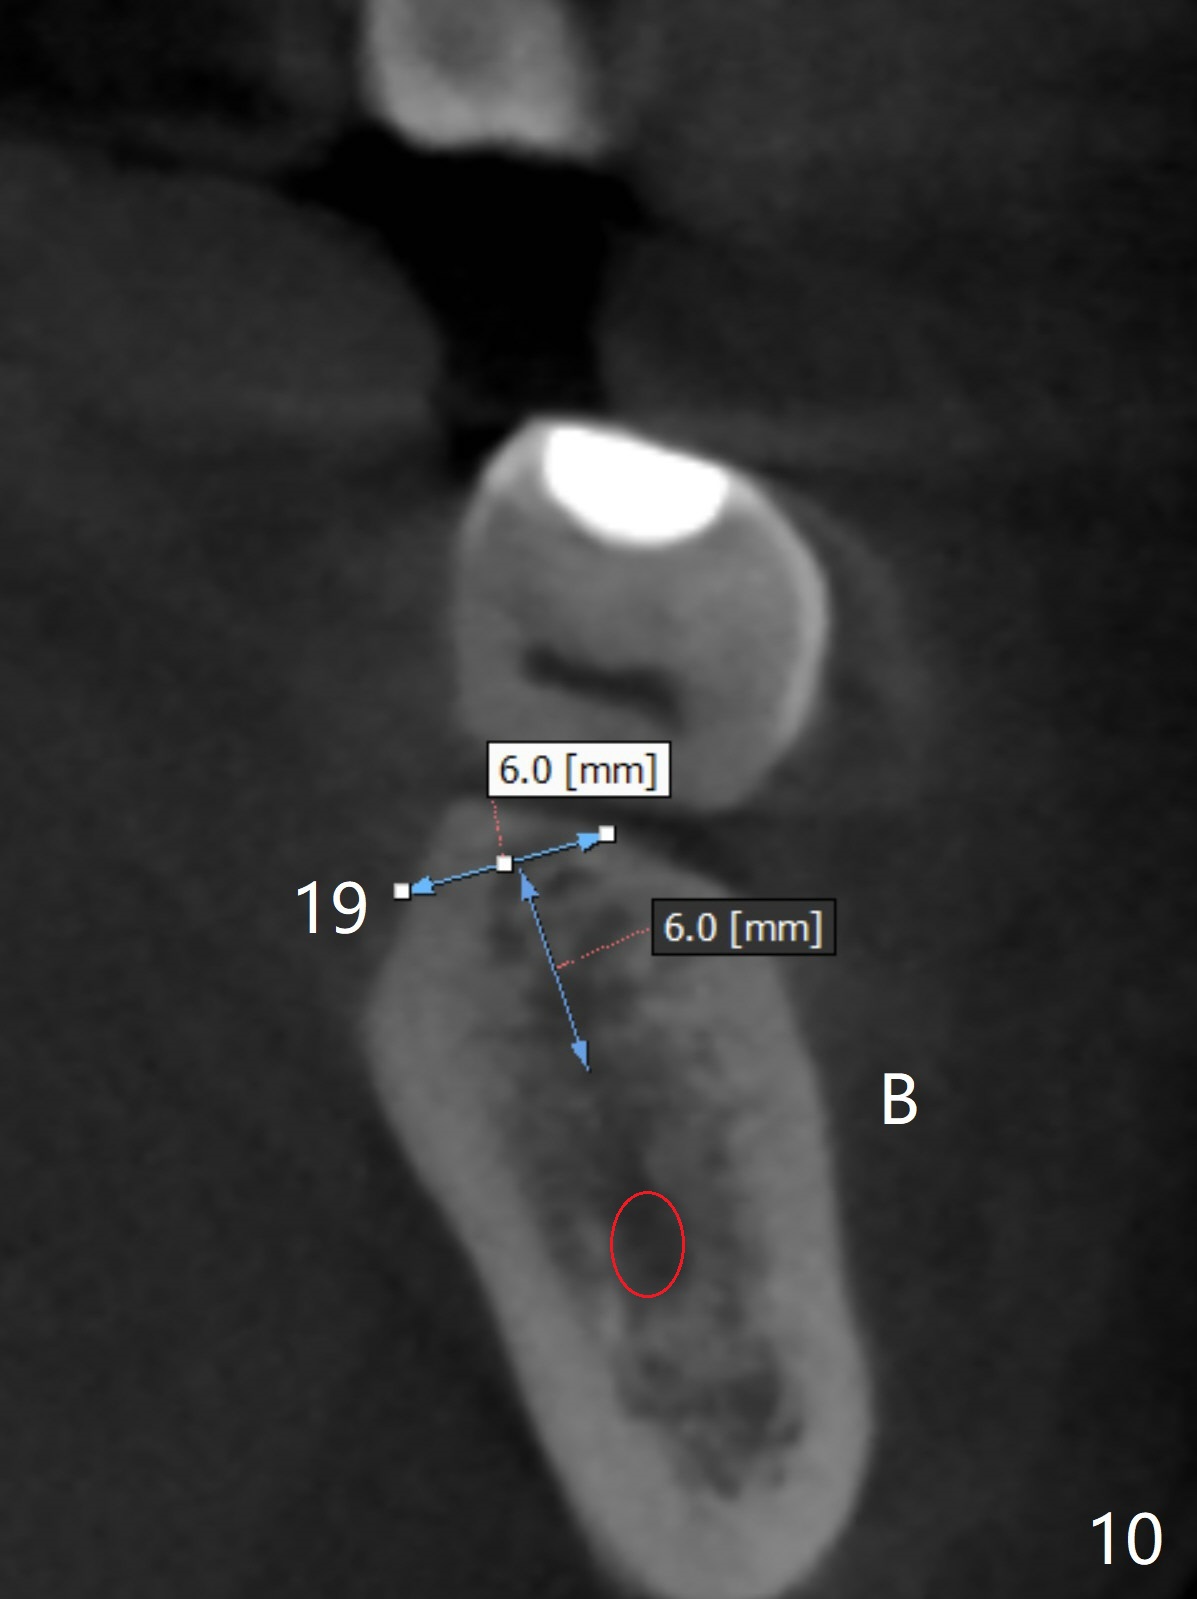

A 43-year-old man has poor dentition on the left: 1st molar missing, 2nd molar mesial inclination (Fig.1) and 2nd bicuspid lingual tilt (Fig.2). The latter is nonfunctional (Fig.3 (linguoposterior view). Two molar implants will be placed in a position so that their crowns will be in cross bite (Fig.4,5), the same occlusal scheme as the teeth #21 and 22. When these implants osteointegrate, the provisional crowns (Fig.6 P) will be supraocclusal so that there is clearance (*) for #20 to upright orthodontically (Fig.7-9). Moreover, these implants will be used anchorage as well as #21 and 22. Panoramic X-ray (Fig.1) and CBCT (Fig.10-12) show limited bone height at the sites of #18 and 19. It appears that 5x8 and 5.9x6 mm implants are appropriate with ridge reduction at #19.